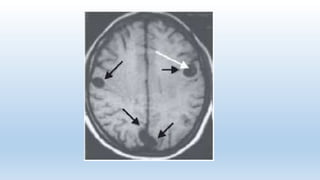

La sospecha clínica y epidemiológica es importante pero el diagnóstico se realiza

primariamente por imágenes y se confirma con serología. La tomografía axial

computarizada y la resonancia magnética

Fases del quiste. Engeneral, la NCC se presenta como formas intraparenquimatosas, asociadas con cuadros convulsivos, o formas extraparenquimatosas, estando estas últimas asociadas con hipertensión endocraneana. Los quistes intraparenquimatosos pasan por las siguientes fases: fase vesicular: quistes viables, provocan una respuesta inflamatoria mínima. fase coloidal: presencia de inflamación provocada por la respuesta inflamatoria celular alrededor del quiste. fase nódulo granular: sustitución gradual por tejido fibrótico y colapso progresivo de la pared del quiste. fase de calcificación: incorporación de calcio sobre el tejido fibrótico del parásito